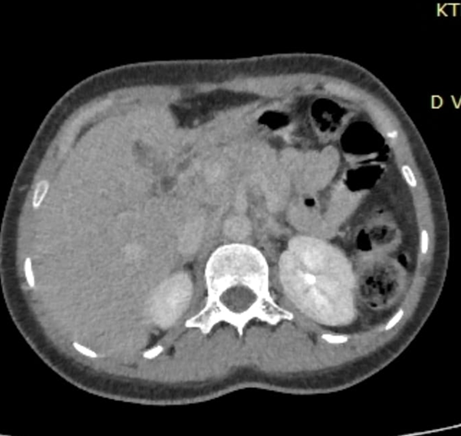

The radiological findings of Triphasic CT scan were highly suggestive of metastatic lymphadenopathy from the primary gallbladder malignancy, causing obstructive cholestasis as shown in (Figure 4).

Figure 4: Suggestive of metastatic lymphadenopathy secondary to primary gallbladder carcinoma, causing obstructive cholestasis